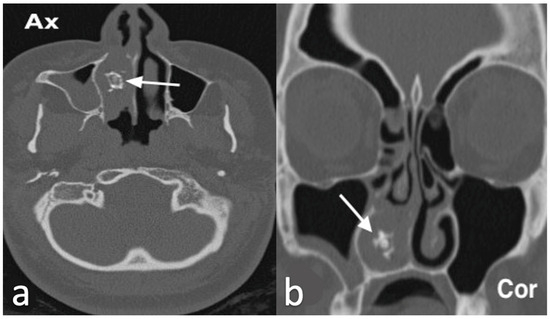

3.2.5. Osteoma